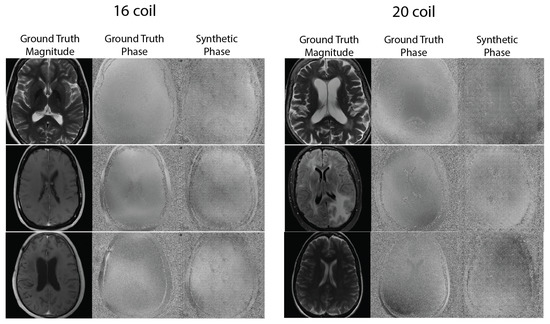

2.2.2. Synthetic Phase Generation